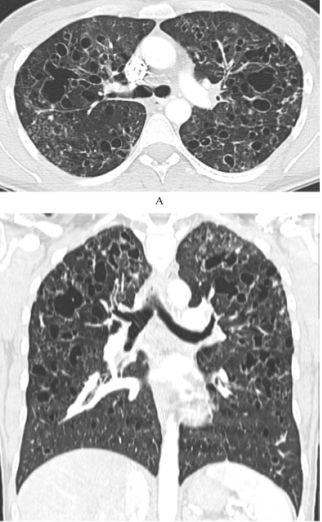

肺朗格汉斯细胞组织细胞增多症(PLCH)要注意囊和结节的特征,它囊性病变的囊壁相对较厚,还可能看到一些结节,所以我们如果看到不规则的、囊壁稍厚、有结节的、分布在中上肺的就一定要注意鉴别PLCH。下面两张影像分别提示我们要注意囊和结节、注意区域分布。

图:PLCH患者的影像,注意囊和结节

图:PLCH患者的影像,注意区域分布